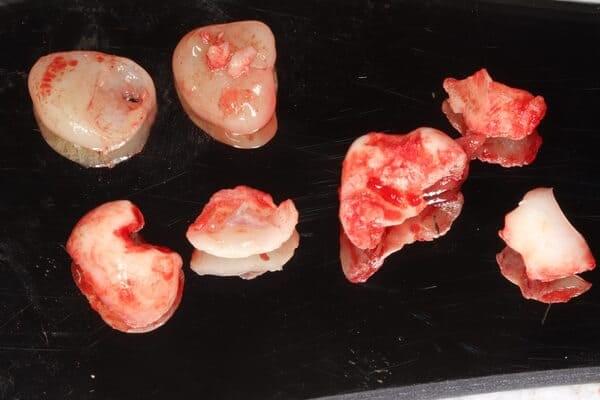

Видалення зубів мудрості. Бродик Богдан.

Видалення зубів мудрості — досить складна процедура, яка потребує високої кваліфікації хірурга. Особливо це стосується ситуації, коли видалення проводиться в ранньому віці. У даному випадку дівчинці 11 років було проведено видалення двох зубів мудрості. Перевага такої тактики полягає в тому, що зуби мудрості видаляються до того, як вони починають негативно впливати на прикус. Це дає дуже багато переваг для формування зубо-щелепної системи, але потребує майстерності лікаря.

Видалення зубів мудрості. Бродик Богдан.

Часто чуємо питання: чи можливо за один візит видалити всі зуби мудрості одномоментно. Так, це можливо, і є ситуації, коли це більш раціонально, ніж розділяти такі маніпуляції на чотири окремі візити. Але в такому випадку це потрібно робити в умовах анестезіологічного забезпечення. У даному клінічному випадку, завдяки ефективній взаємодії з анестезіологічною командою, було проведено одномоментне видалення чотирьох зубів мудрості. Тепер пацієнтка скерована до ортодонта і готова розпочинати ортодонтичне лікування.